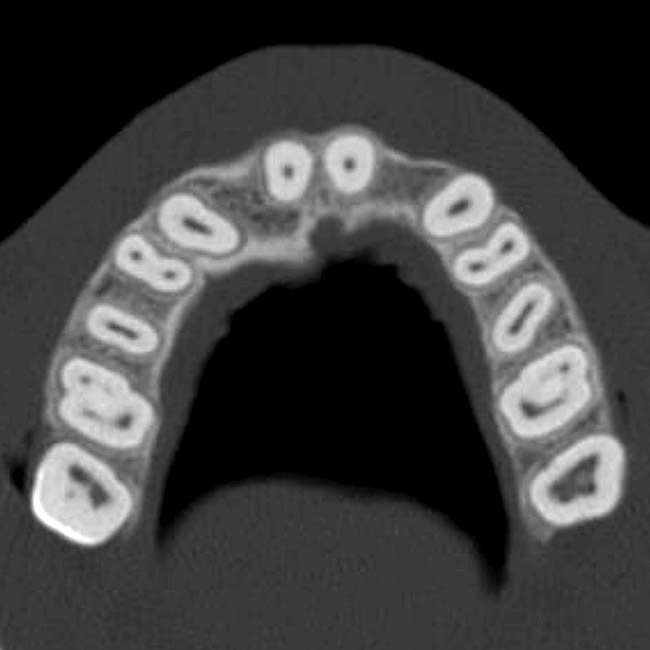

The CT axial views represent an important instrument in gaining a better understanding of anatomical features that can not be determined by any other imaging modality (Figure 6A). When the maxilla is sliced axially at the level where the roots meet the crest of the bone, the adjacent and surrounding root morphology can be revealed. Of note are the individual and different shapes of each of the central incisors, canines, premolars, and molar roots. These images reflect a phenomenon defined by the author as the “restorative dilemma.” Clinicians encounter this often difficult dilemma when attempting to re-establish morphologically correct emergence profiles in prosthetic teeth as they ascend from the round shape of the implant(s). When planning for the placement of the implant in the left lateral incisor area, there appeared to be adequate mesial-distal space between roots as seen in the axial view of Figure 6B. A closer inspection of the planned site for the right lateral incisor revealed a more narrow space, further.complicated by the distal rotation of the palatal aspect of the tooth root. Based on this preliminary position, the 3.75-mm diameter, straight-walled implant can be seen encroaching on the lamina dura periodontal ligament space of the right canine and central incisor. If there was not adequate room for this diameter and type of implant, the adjacent teeth could sustain potential iatrogenic damage. Therefore, additional “tweaking” of the virtual placement was necessary to diminish this risk.

Figure 6a  By slicing the maxilla axially, the images revealed (A) the differing morphology of the central incisors, canines, premolar, and molar roots, and (B) the left simulated implant seen encroaching on the adjacent lamina dura.

Figure 6a

Figure 6b  By slicing the maxilla axially, the images revealed (A) the differing morphology of the central incisors, canines, premolar, and molar roots, and (B) the left simulated implant seen encroaching on the adjacent lamina dura.

Figure 6b